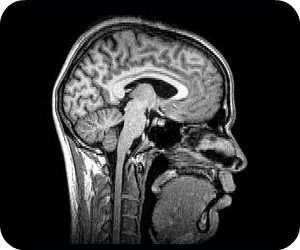

La tomografía computarizada es un procedimiento para diagnóstico con imágenes, también conocida como exploración por TC o TAC, muestra un corte o sección transversal del cuerpo muestra huesos, órganos y tejidos blandos, muestra lo necesario para poder observar la estructura interna, el procedimiento es indoloro.